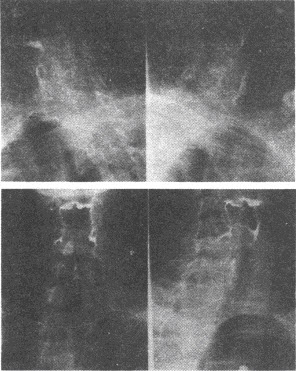

(多选题)该病例组织学分型分为哪三型()

A:上皮细胞型

B:淋巴细胞型

C:血管型

D:脂肪细胞型

E:混合型

F:纤维细胞型